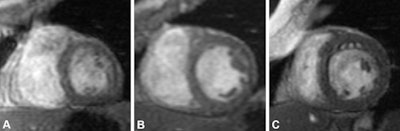

Example of noncontrast short-axis cardiac MRI scans of the heart at end diastole in participants with varying left-to-right ventricular volume ratios (LRVRs). (A) Image in a 78-year-old male with right ventricle (RV) predominance (LRVR < 0.8) with an LRVR of 0.56, left ventricular end-diastolic volume indexed to body surface area (LVEDVi) of 44.44 mL/m2, and right ventricular end-diastolic volume indexed to body surface area (RVEDVi) of 79.88 mL/m2. (B) Image in a 65-year-old male with balanced left ventricle (LV)–RV with an LRVR of 1, LVEDVi of 62.07 mL/m2, and RVEDVi of 62.07 mL/m2. (C) Image in a 74-year-old female with LV predominance (LRVR > 1.3) with an LRVR of 2.06, LVEDVi of 94.81 mL/m2, and RVEDVi of 46.1 mL/m2. Images and caption courtesy of the RSNA.